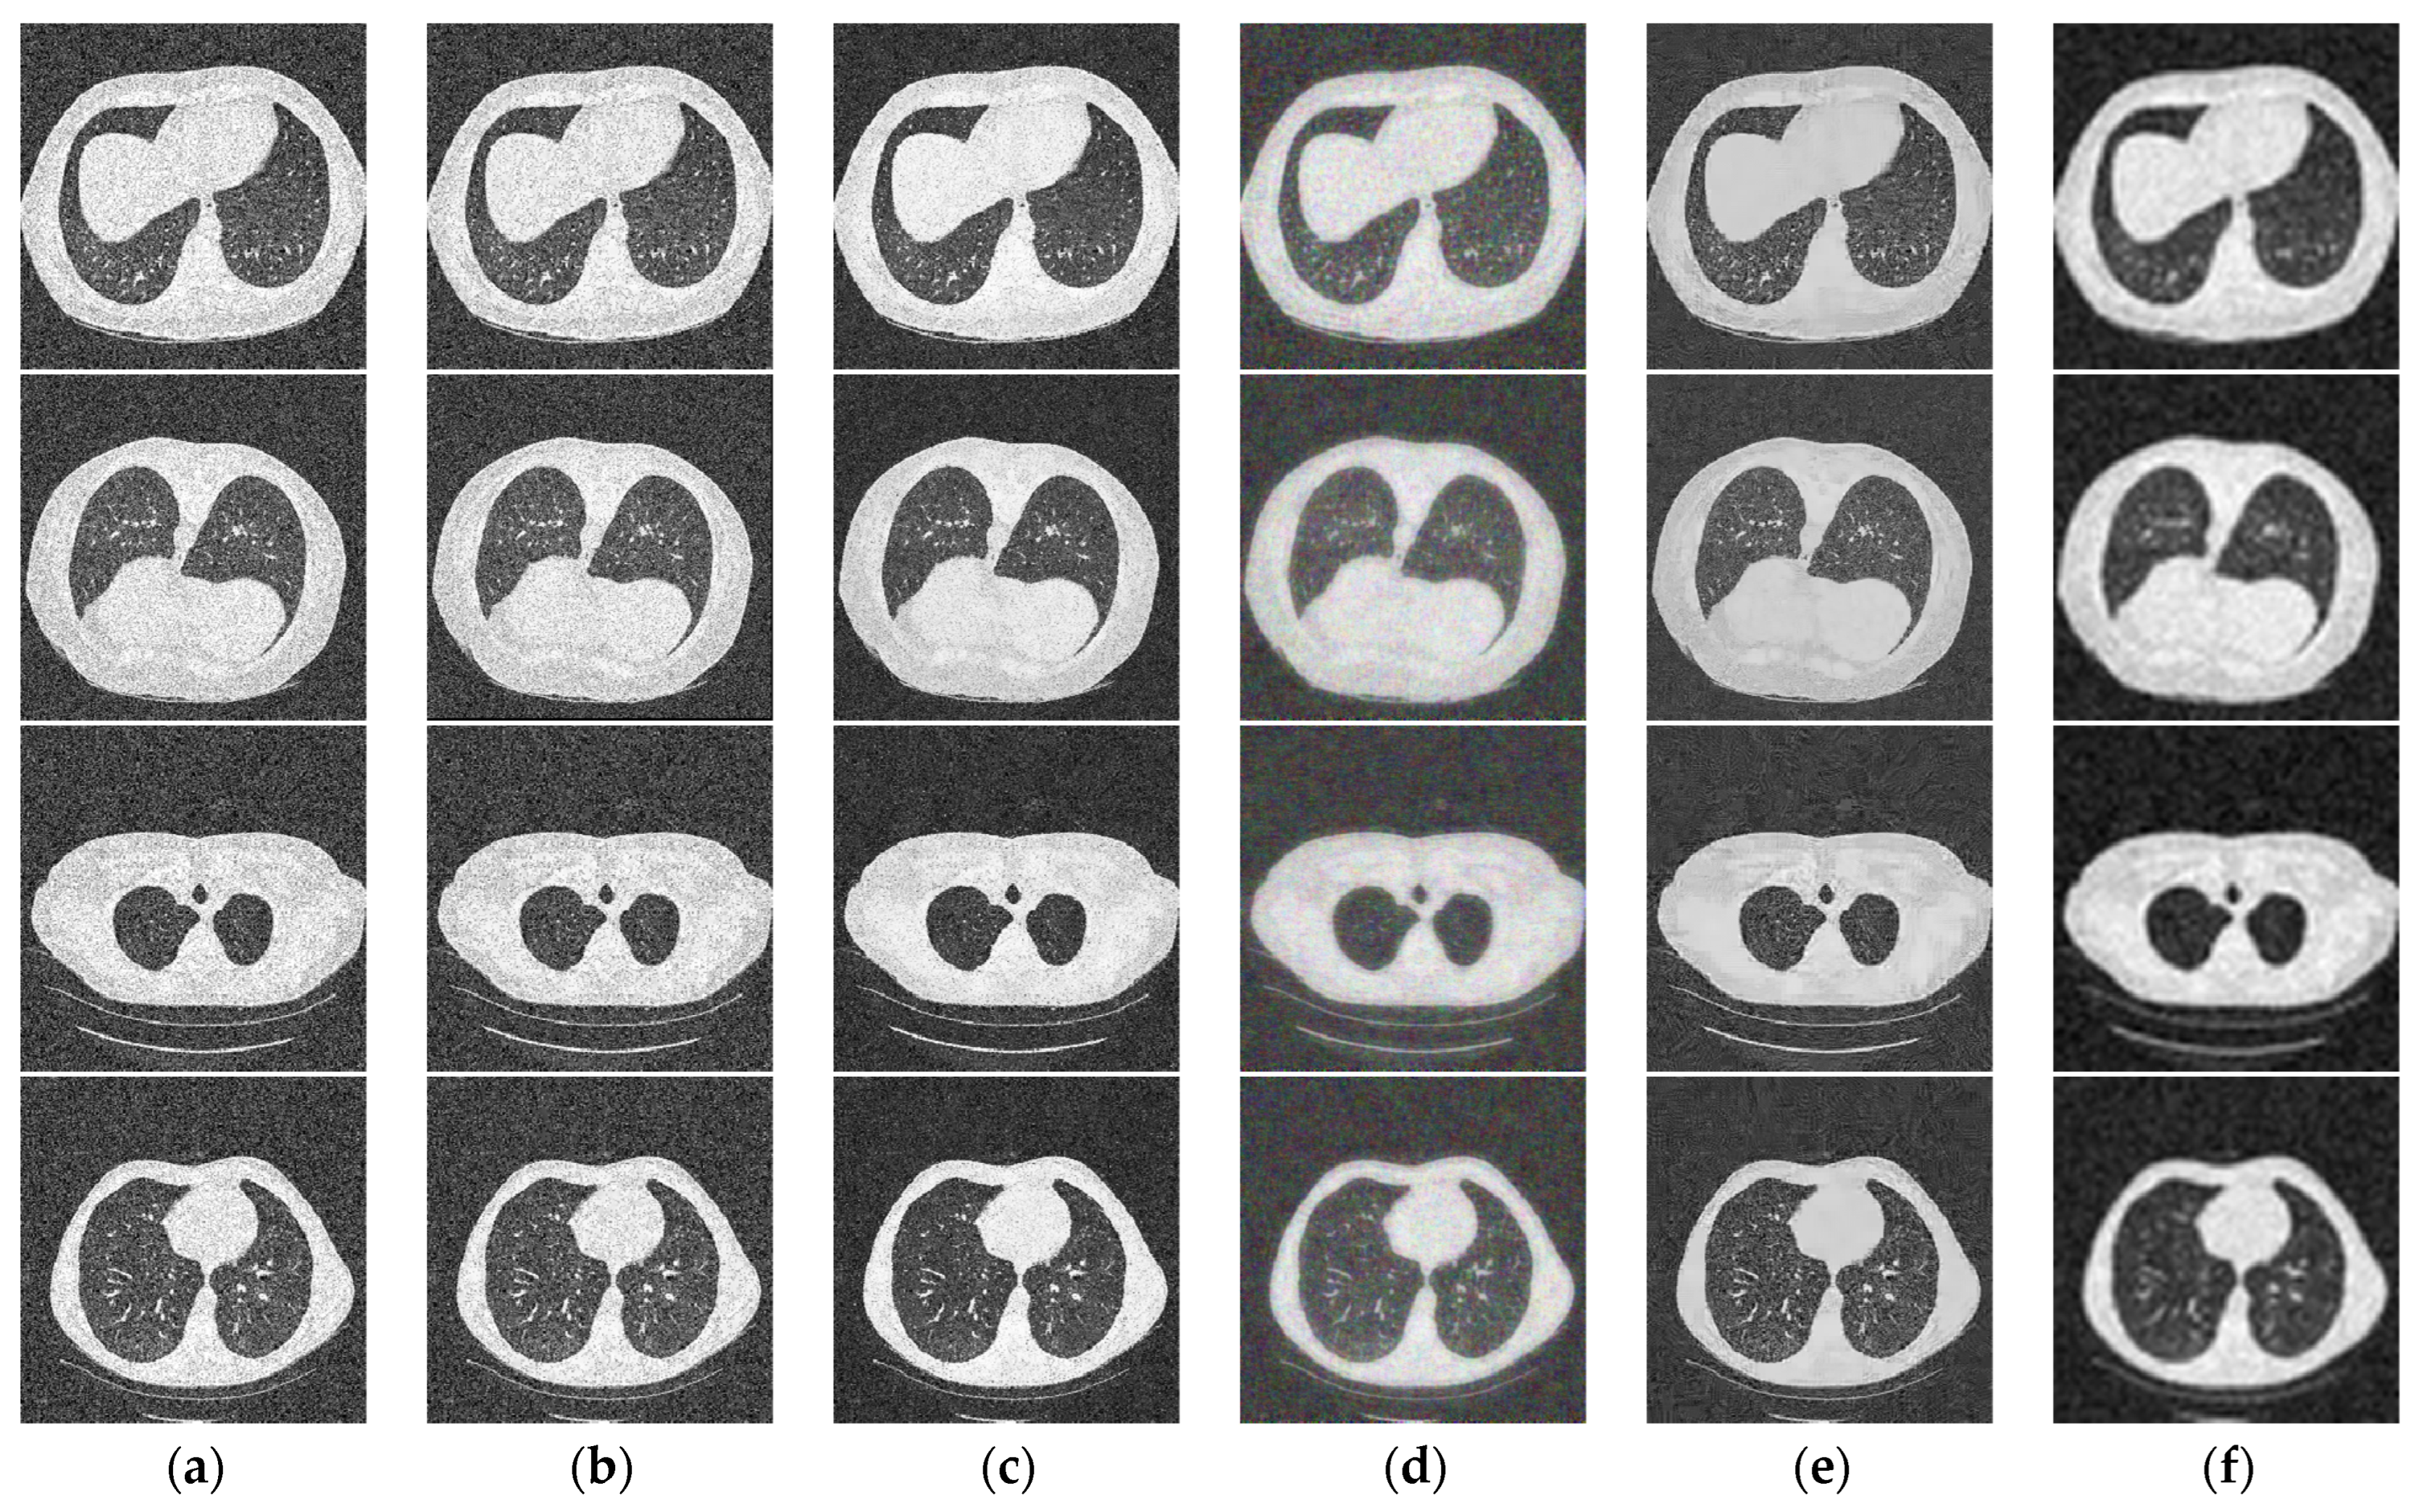

4. Experiment

5. Discussion

| Image | I1 | I2 | I3 | I4 | ||||

|---|---|---|---|---|---|---|---|---|

| Metrics | PSNR | SSIM | PSNR | SSIM | PSNR | SSIM | PSNR | SSIM |

| AD | 18.48 | 0.2964 | 18.38 | 0.2407 | 18.42 | 0.2352 | 18.27 | 0.3298 |

| BF | 20.37 | 0.3593 | 19.95 | 0.3004 | 20.21 | 0.2965 | 19.71 | 0.3731 |

| KSVD | 22.61 | 0.5578 | 22.49 | 0.3787 | 23.34 | 0.5512 | 22.67 | 0.5660 |

| BM3D | 20.66 | 0.5479 | 23.63 | 0.5736 | 22.80 | 0.4603 | 21.15 | 0.4830 |

| W-NMM | 22.67 | 0.6219 | 24.20 | 0.6798 | 23.62 | 0.6557 | 22.43 | 0.6714 |